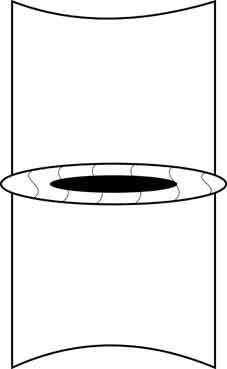

Но при дистрофических процессах в диске ядро уменьшается в размерах, связки фиброзного кольца ослабевают без поддержки изнутри и в сегменте возникает гипермобильность – так называемая ортопедическая стадия остеохондроза.

Тело вышележащего позвонка обретает дополнительную степень свободы, и может смещаться в горизонтальной плоскости чаще кзади, что обусловлено строением дугоотросчатых суставов (так называемый «дегенеративный сдвиг»). Кроме того, увеличивается и вертикальная подвижность краёв соседних позвонков, что при форсированных сгибании и разгибании приводит к возникновению отрицательного давления в «полости» межпозвонкового диска и как следствие этого к появлению «вакуум-феномена».